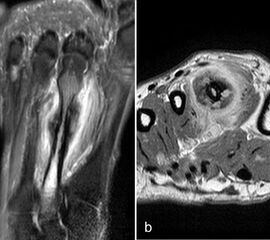

Zwischen der plantaren Platte und der Grundphalanx ist in der Mittellinie des Gelenkes ein kleiner Rezessus vorhanden (Abb. 9).

Dieser flüssigkeitsgefüllte Raum darf nicht als Ruptur der plantaren Platte fehlinterpretiert werden 23. Verletzungen der plantaren Platte erfassen immer auch den medialen oder lateralen Zügel.